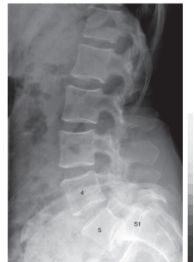

9

-Refer to the figure. What abnormality is present at L5-S1?

A) Spondylolisthesis

B) Spina bifida

C) Spondylosis

D) Scoliosis